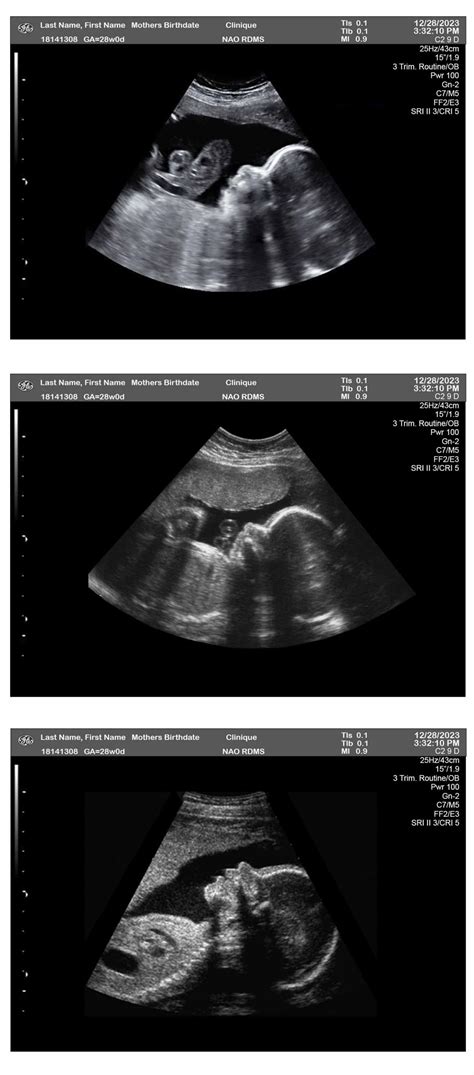

28 Weeks Sonography is a routine ultrasound scan conducted during the third trimester of pregnancy. This scan is often referred to as the "anomaly scan" or "mid-pregnancy scan" and is usually performed between 26 and 28 weeks of gestation. The primary goal of this ultrasound is to assess the baby's growth, development, and overall health. It also helps in identifying any potential complications that may require further monitoring or intervention.

During a 28 Weeks Sonography scan, the expectant mother will lie on an examination table with her abdomen exposed. A gel is applied to the abdomen to enhance the transmission of ultrasound waves. A transducer, a handheld device, is then moved over the abdomen to capture images of the baby. The procedure is painless and non-invasive, typically lasting between 20 to 30 minutes.

These measurements help in estimating the baby's weight and assessing overall growth. The technician will also check for any structural abnormalities in the baby's organs, such as the heart, brain, kidneys, and spine.

After the 28 Weeks Sonography scan, the ultrasound technician will review the images and measurements with the expectant mother. The results are typically discussed with the obstetrician, who will interpret the findings in the context of the mother's overall health and pregnancy history. Key points to consider include:

• Growth Parameters: The measurements of the baby's head, abdomen, and femur are compared to standard growth charts to ensure the baby is developing normally.

• Organ Function: The scan assesses the function and structure of the baby's organs, looking for any signs of abnormalities.